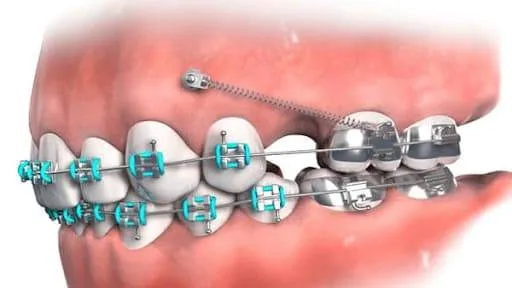

Ai cũng muốn có một hàm răng đẹp, trắng sáng và đều để tự tin khi giao tiếp. Tuy nhiên, với một số người bị móm, hô